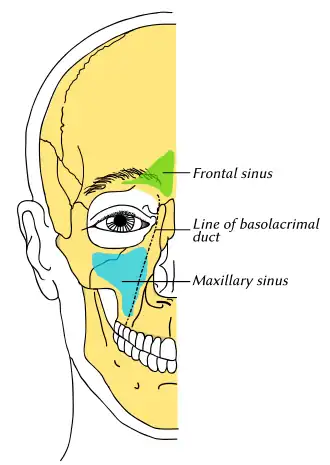

Outline of bones of face, showing position of air sinuses. Maxillary sinus is shown in blue. | |

The pyramid-shaped maxillary sinus (or antrum of Highmore) is the largest of the paranasal sinuses, located in the maxilla. It drains into the middle meatus of the nose[1][2] through the semilunar hiatus. It is located to the side of the nasal cavity, and below the orbit.[2]

It is the largest air sinus in the body.[1][3] It has a mean volume of about 10 ml.[1] It is situated within the body of the maxilla,[1][3][4] but may extend into its zygomatic and alveolar processes when large. It is pyramid-shaped, with the apex at the maxillary zygomatic process, and the base represented by the lateral nasal wall.[4]

It has three recesses: an alveolar recess pointed inferiorly, bounded by the alveolar process of the maxilla; a zygomatic recess pointed laterally, bounded by the zygomatic bone; and an infraorbital recess pointed superiorly, bounded by the inferior orbital surface of the maxilla. The medial wall is composed primarily of cartilage.[1][3]